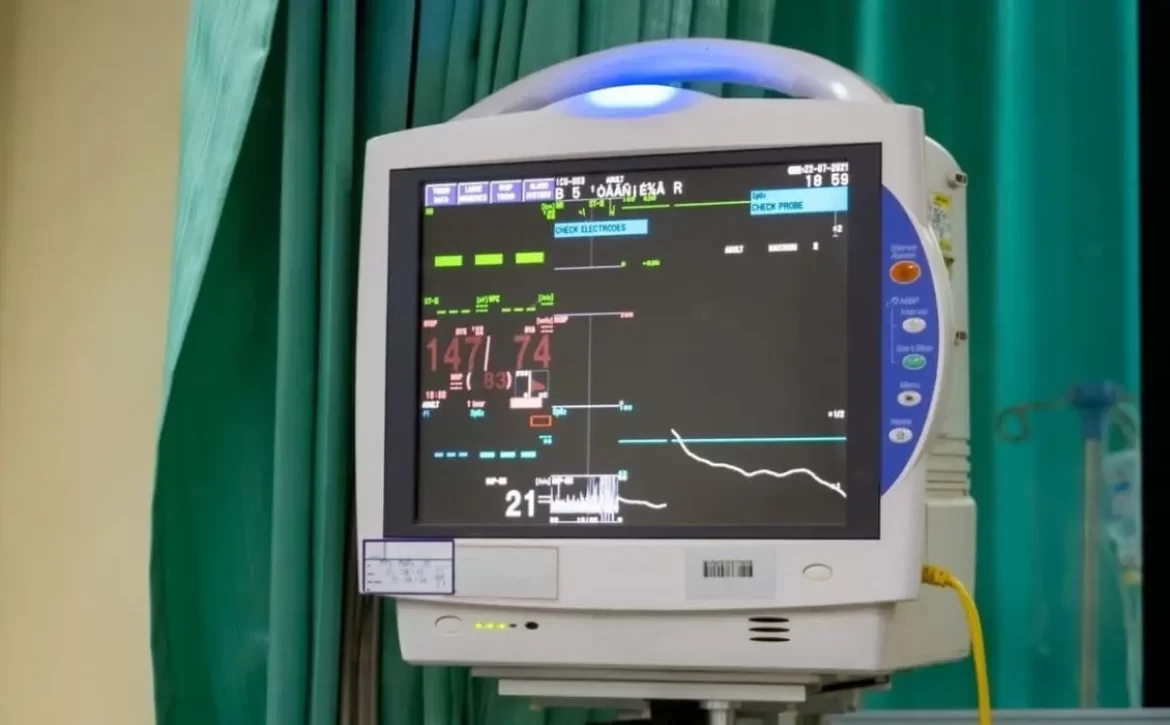

امروزه با استفاده از «تلهمانیتورینگ»، پزشک میتواند از راه دور علائم حیاتی بیمار را روی گوشی هوشمند خود مشاهده کند. این فناوری، دغدغه اصلی در انتقال بیمار از ICU به منزل که همان نظارت تخصصی است را برطرف کرده است. بیمارستان مجازی ایران با استفاده از این ابزارها، فاصله بین خانه و بیمارستان را از بین برده است.